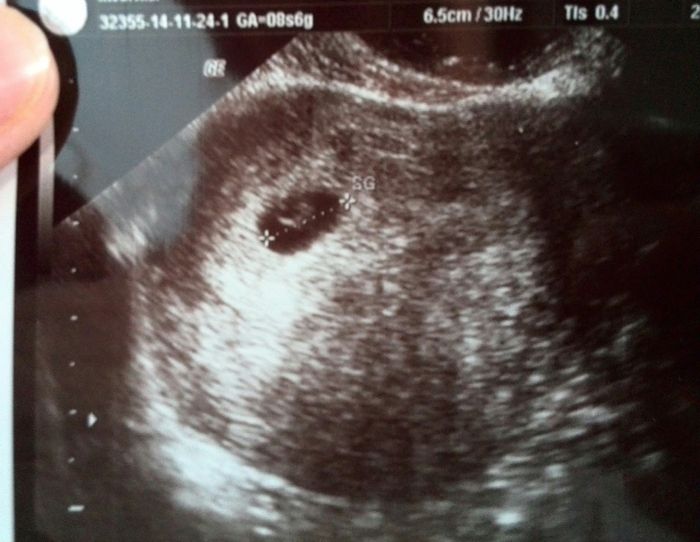

Ragazze ieri prima visita...che emozione incredibile!so che é assurdo, che é cosi minuscolo e che non é il caso di agitarsi cosi alla 5 settimana maaa...sono innamorata persa già di quei pochi mm di vita..auguro a tutte le donne che stanno cercando,...